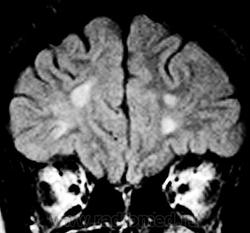

ГМ. Рассеянный склероз 3. +

Рассеянный склероз